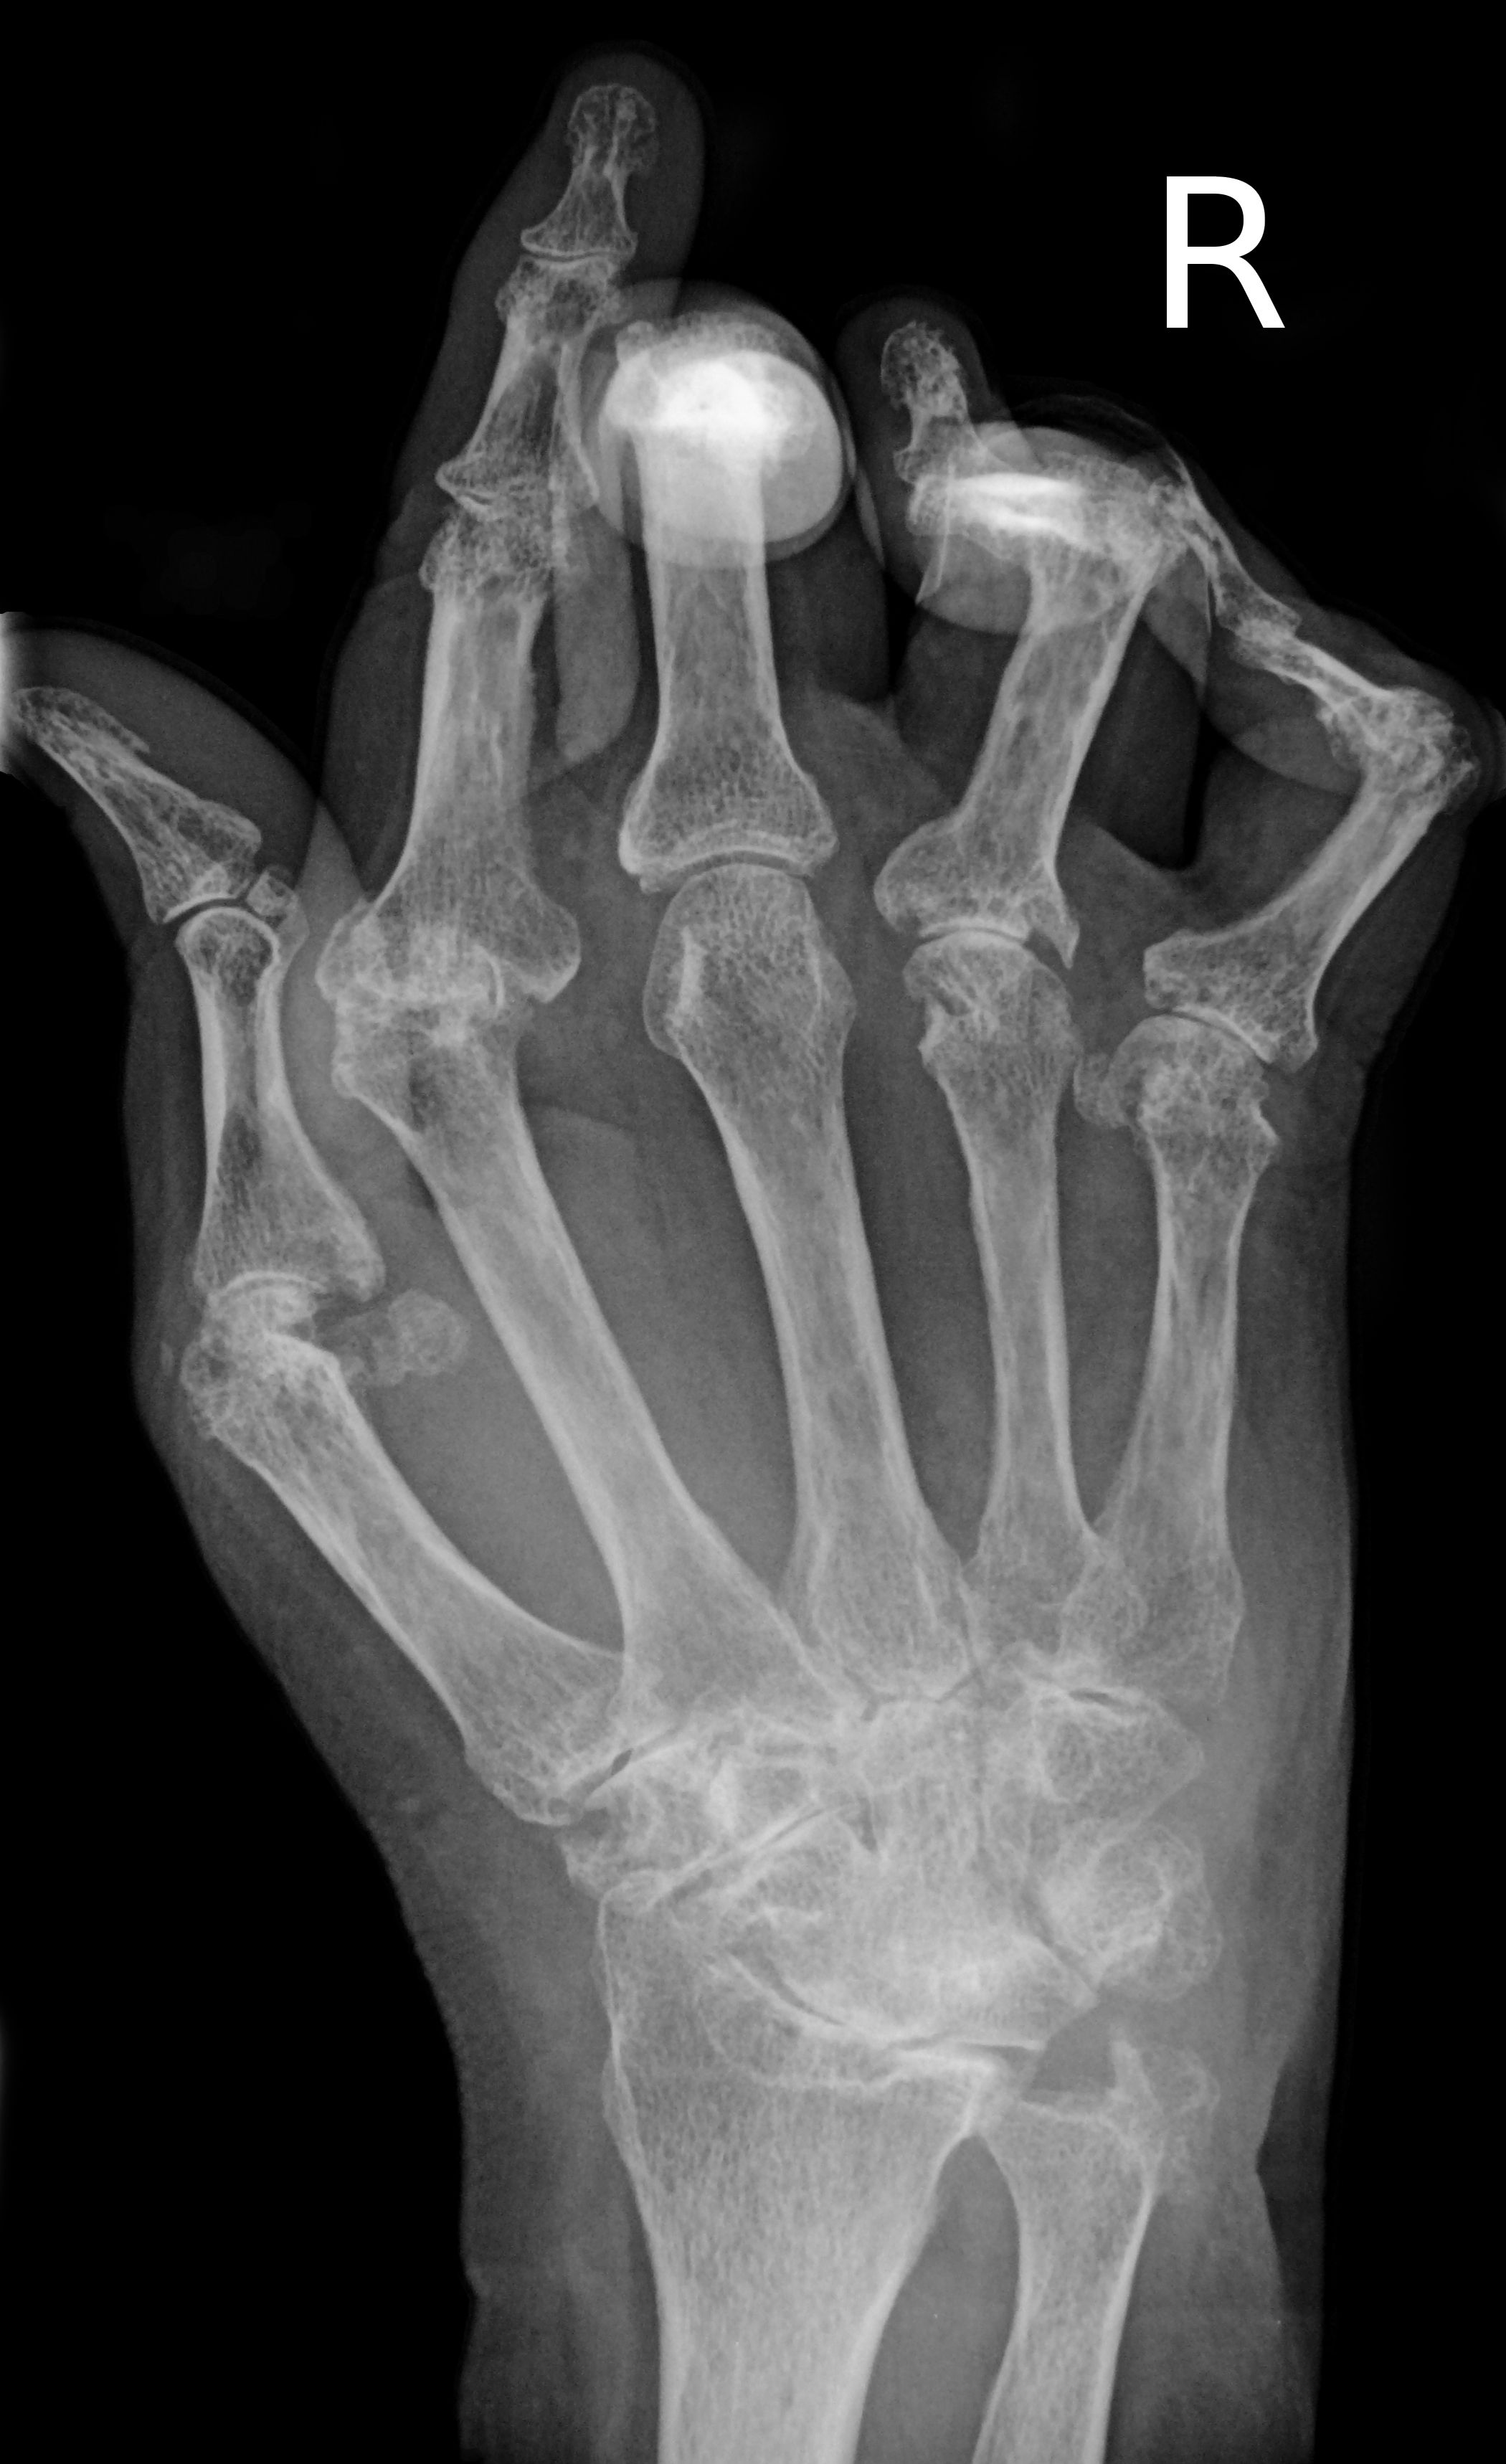

류마티스 관절염은 자가면역 질환으로, 관절의 통증, 뻣뻣함, 부종을 특징으로 한다. 정확한 원인은 밝혀지지 않았지만, 유전적 요인, 환경적 요인, 면역 체계의 이상이 복합적으로 작용하는 것으로 알려져 있다. 관절 증상 외에도 피부, 폐, 심혈관 등 다른 장기에도 영향을 미칠 수 있으며, 조기에 진단하고 치료하면 증상 완화와 관절 손상 지연이 가능하다. 치료에는 약물 치료, 운동, 물리 치료 등이 사용되며, 심한 경우 수술적 치료가 고려될 수 있다. 류마티스 관절염의 예후는 다양하며, 조절되지 않는 만성 염증은 수명 단축 및 심혈관 질환 위험 증가와 관련이 있다.

류마티스 관절염의 주요 증상은 관절의 통증, 뻣뻣함, 부종이다. 주로 활막의 염증으로 인해 발생하며, 시간이 지남에 따라 여러 관절에 영향을 미치는 다발성 관절염으로 진행된다. 손, 발, 경추의 작은 관절뿐만 아니라 어깨나 무릎과 같은 큰 관절에도 영향을 줄 수 있다.[19]

- 변형: 염증이 진행되면서 힘줄 고정, 관절 표면 침식 및 파괴로 인해 운동 범위가 손상되고 변형이 발생한다. 손가락에는 척골 편위, 버튼홀 변형, 백조 목 변형, "Z 엄지" 등 다양한 변형이 나타날 수 있다.[19] 망치 발가락 변형도 나타날 수 있다.[20]